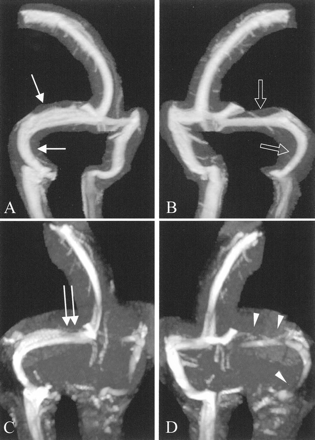

图2。系统的原理图用于分级横向的开放和乙状窦。每个左翼和右翼的年级transverse-sigmoid管道分别确定和定义的最高程度的狭窄远端从torcula遇到乙状窦并给予相应的数字从0到4。0 =不连续(gap)或再生障碍性段;1 =发育不全或严重狭窄段的管道内估计不到25%的横截面直径的远端上矢状窦腔;2 =中度狭窄的部分管道(25 - 50%),3 =轻度缩小部分(50 - 75%);和4 =无显著缩小(75 - 100%)。左翼和右翼的和合并后的管道提供得分(CCS)和通常范围从2 - 8。(A)正常情况下,每一个左翼和右翼管道将得分4的合成CCS 8,和(B, C,以及D)示意图CCS 4的例子,3,1。